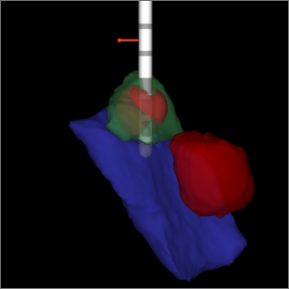

We have accepted the challenge to improve this process. Our solution: Image Guided DBS provides your physician the ability to see exactly where your leads are located and exactly where your stimulation needs to be delivered.

We hear often – How do you know the leads are in the right place? Or if my condition changes, can my therapy change too? Image Guided DBS answers both questions.

See how Image Guided DBS works:

Collected images are evaluated to see the exact location of your leads.

The images are loaded into the programming software and therapy is programmed precisely – based on the location of your leads.